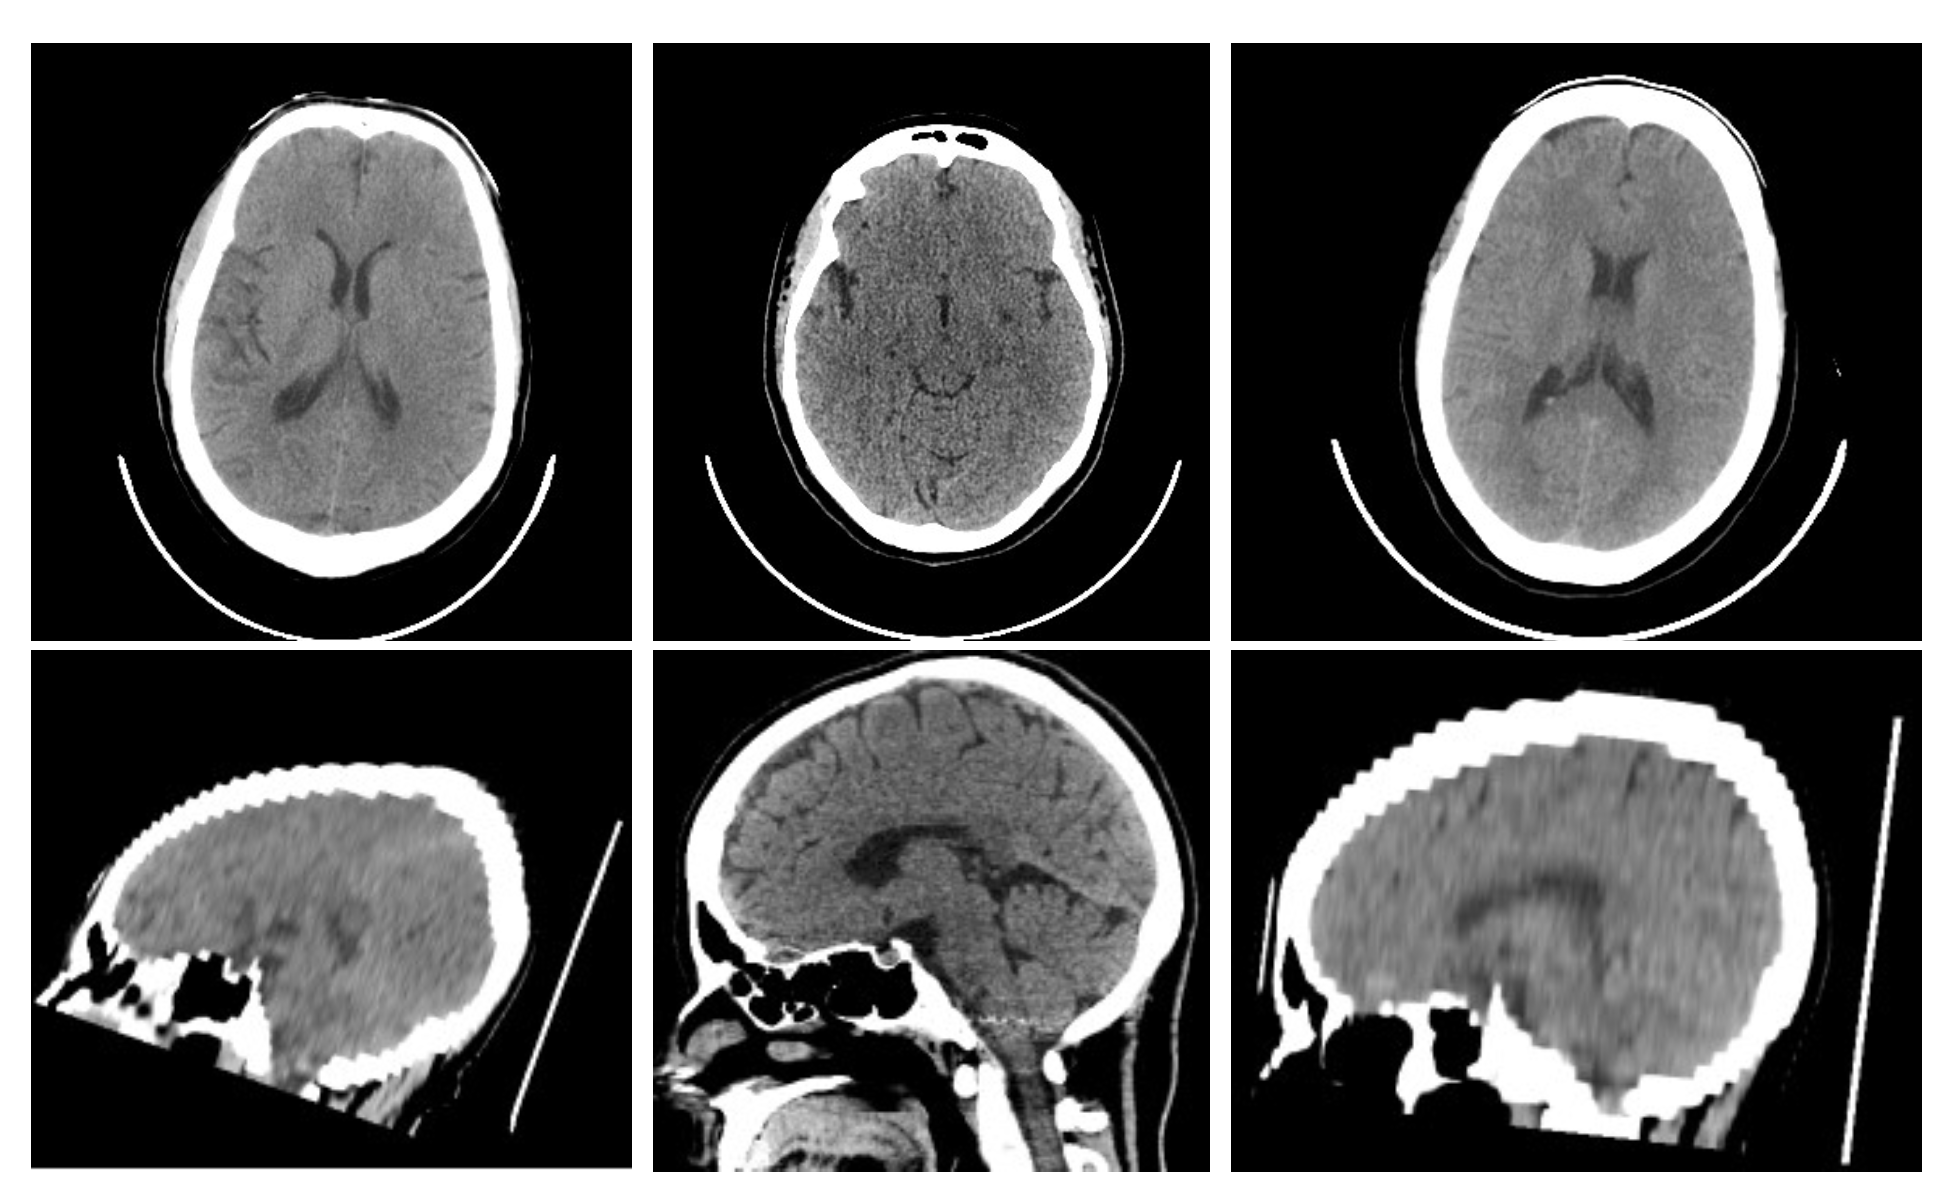

3.1. Dataset